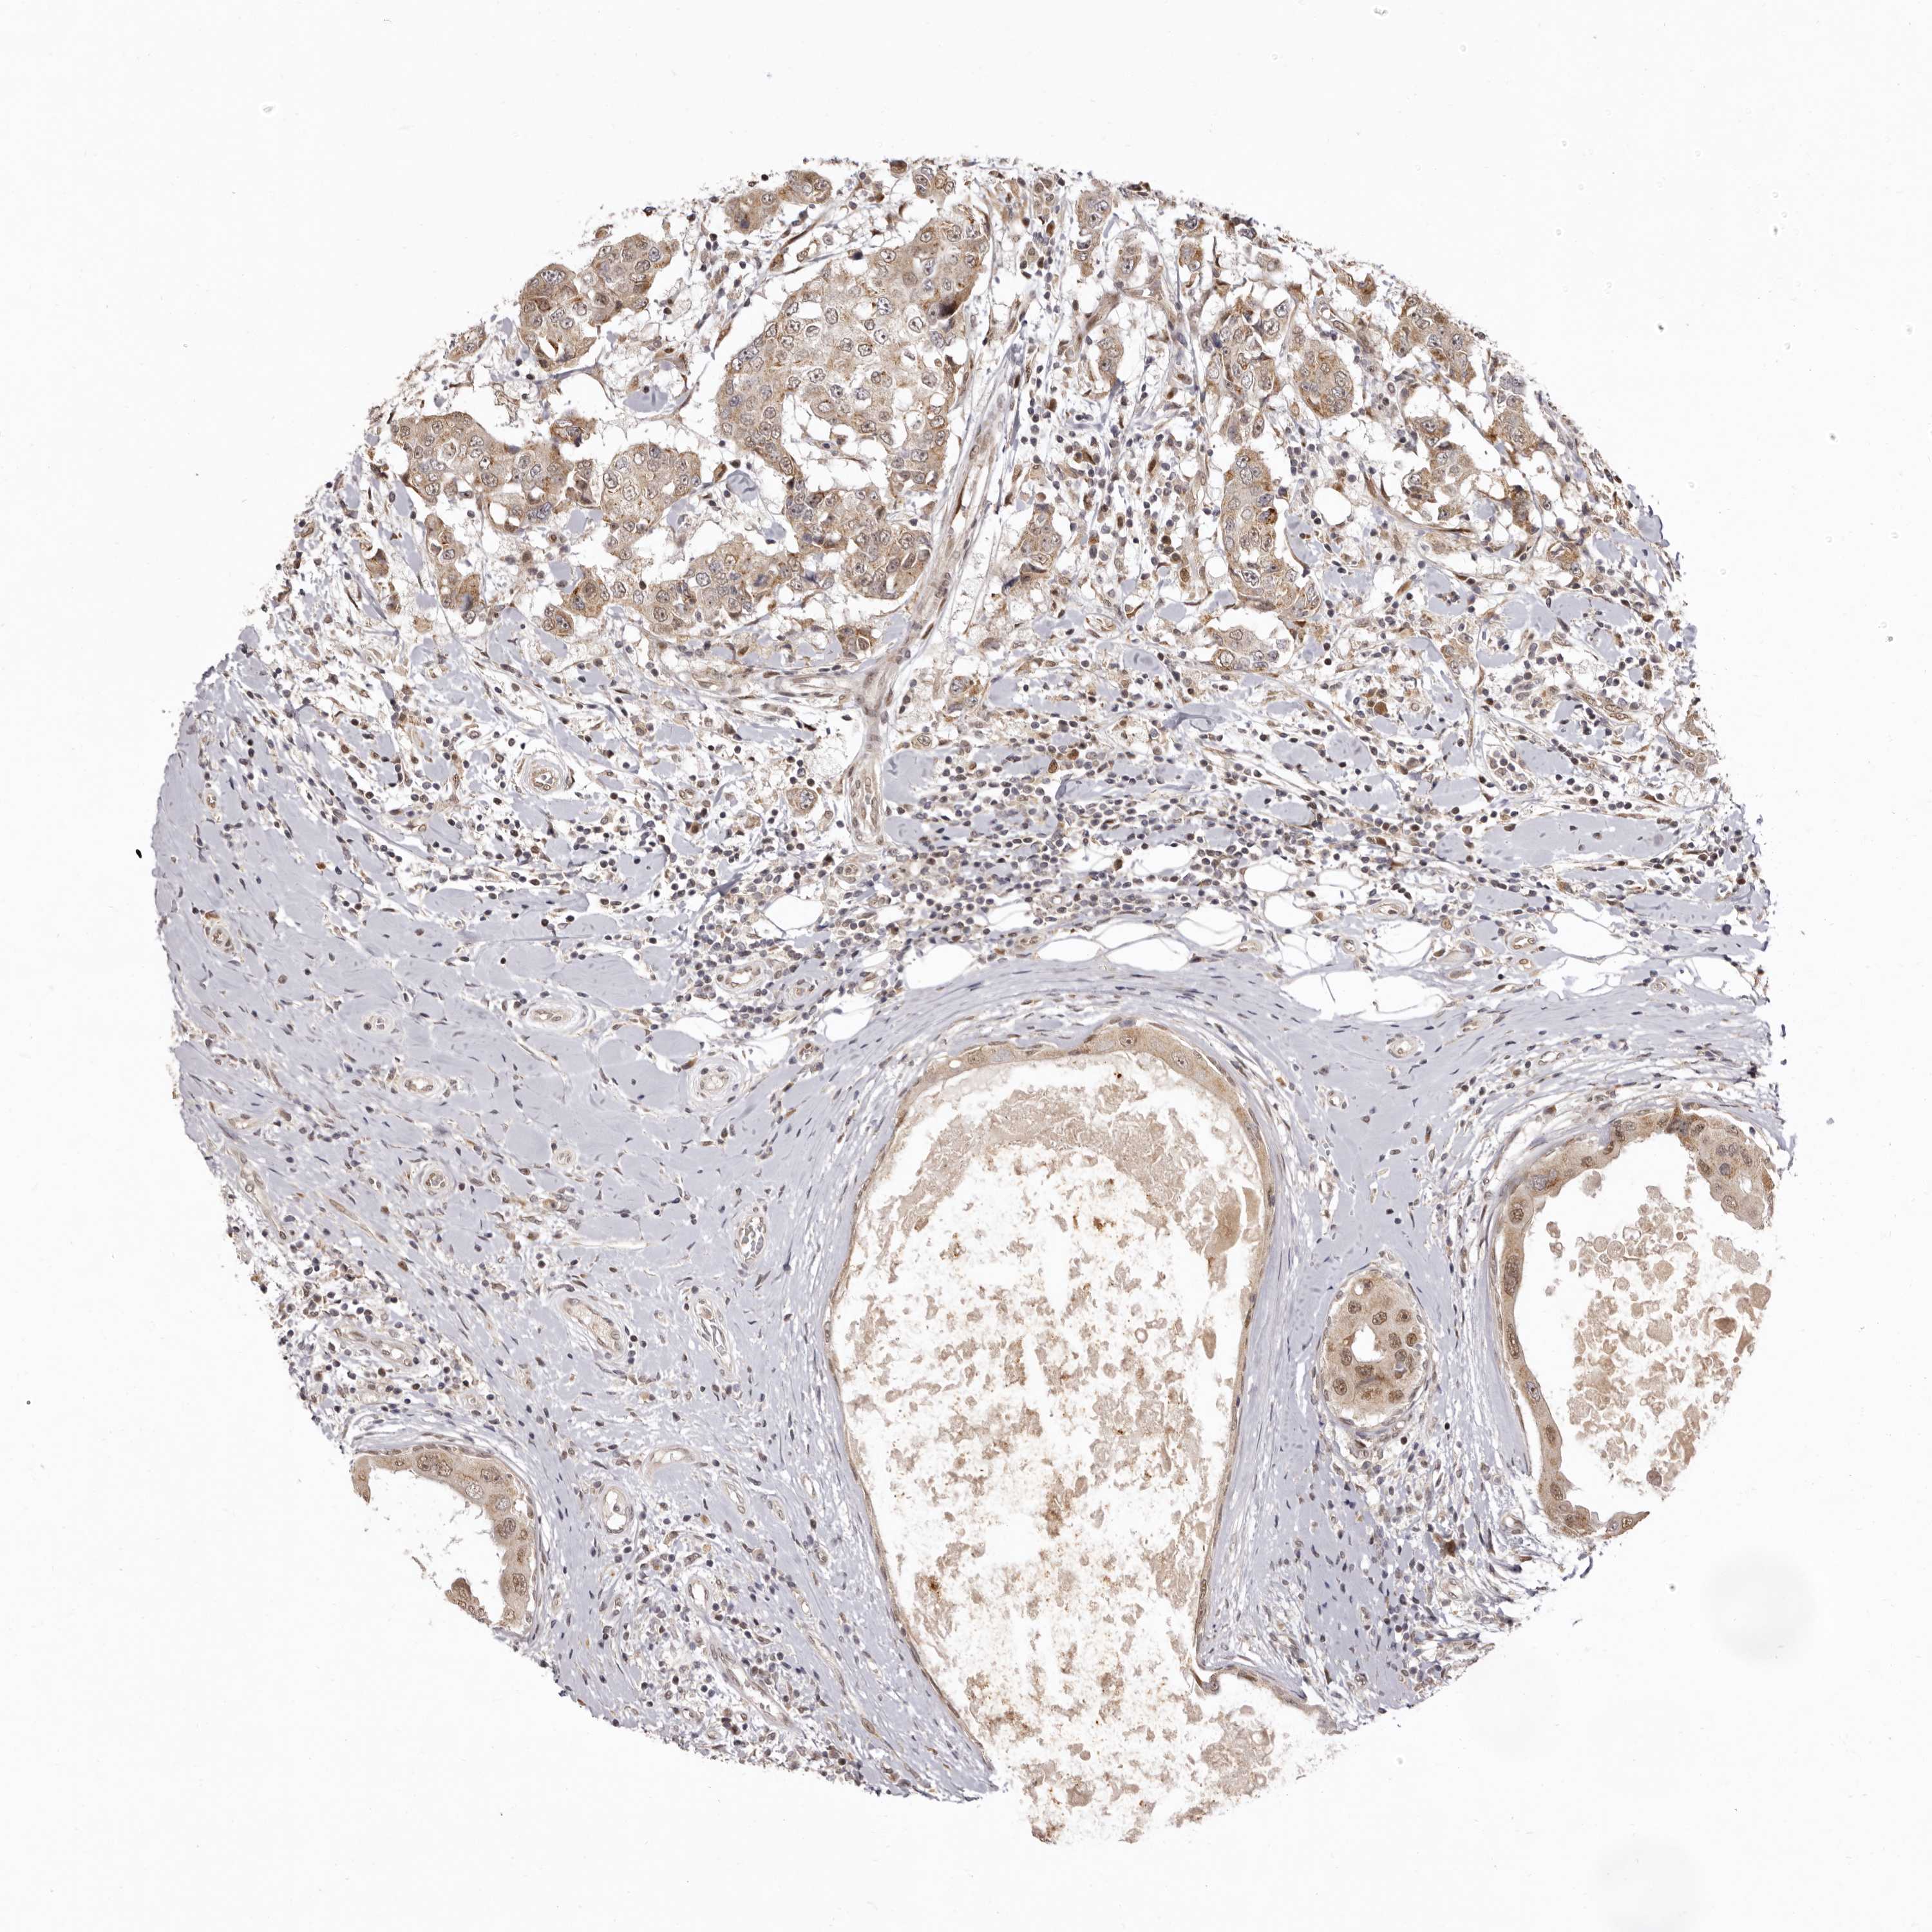

CANCER BREAST CANCER Show tissue menu

BRCA TCGA BRCA VALIDATION PROTEIN EXPRESSION

ANTIBODIES

AND

VALIDATION